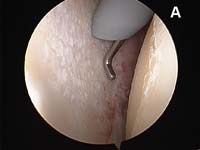

- the rotator cuff tear is identified and loose, degenerated, and frayed tissue around the cuff edge must be removed back to healthy tissue. This process is called débridement.

For the most common type of rotator cuff tears, the tendon of the rotator cuff muscle called the supraspinatus will have torn and pulled back slightly from its normal attachment at the greater tuberosity atop the humerus. These smaller tears which are "non-retracted" or "minimally-retracted" only need to be freshened or débrided back to stable, healthy tendon tissue, then mobilized back to the tuberosity and fixed in place. (See Fig. 9) When using an all arthroscopic technique, the surgeon will employ special devices called "suture anchors" to hold the tear in position when it heals. These "anchors" can be made of metal or absorbable compounds. They are screwed or pressed into the bone of the attachment site and the attached sutures are used to tie the edge of the rotator cuff in place.